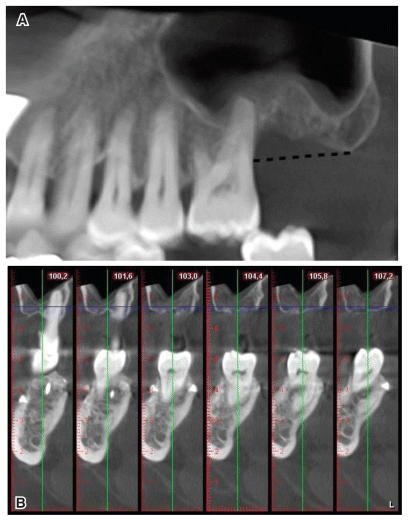

The present case report as redacted following the CARE guidelines (https://www.care-statement.org/). In January 2022, a 51-year-old male patient presented to our clinic seeking prosthetic implant rehabilitation for tooth 27, which was lost 9 years ago. The patient was classified as American Society of Anesthesiologists (ASA)-1, under the ASA Physical Status Classification System, has no significant health concerns. He was a nonsmoker and maintained a good level of oral hygiene. His medical history revealed no systemic contraindications to oral surgery. Objective and radiographic examinations showed a probing pocket depth (PPD) value of 4 mm and a clinical attachment level (CAL) of 9 mm on tooth 26. The vertical deficit of the alveolar process at site 27, measured using cone beam computer tomography (CBCT) with Romexis software (Planmeca, Helsinki, Finland), was 7 mm (Fig. 1a–b). The objective of the surgical treatment was to achieve 3D bone regeneration of the supracrestal effect at site 27 while simultaneously promoting periodontal regeneration in the distal portion of tooth 26. Additionally, qualitative and quantitative restorations of the thickness of the atrophic supracrestal soft tissue were planned to achieve the optimal biological width around the implant. A two-stage surgical and regenerative treatment was proposed; the first stage aimed to regenerate the supracrestal hard tissue while addressing the periodontal defect affecting the adjacent natural tooth, while the second surgery involved the removal of the nonresorbable devices, implant insertion, and enhancement of the supracrestal soft tissue using the connective tissue graft (CTG) technique. A virtual case resolution project was developed using 3D processing software according to there generation and guided prosthetic implantology guidelines.5 The patient was informed about the study and the collection of data and images related to his case. A signed informed consent form was obtained from the patient according to ethical standards.

The patient was recalled 6 months after the first operation, and a new CBCT scan was performed to evaluate the maturation of the bone graft and plan the implant insertion. The scan showed a 3D increase in the residual alveolar process and a reduction in the periodontal defect (Figs. 3a–3b). The digitally calculated distance between the bone crest and the maxillary sinus floor was 8 mm. Therefore, a 3-mm crestal elevation was planned at the same time as the insertion of a 10-mm-long implant with a transmucosal portion of 1.8 mm (3c). Loss of the vestibular fornix following the first operation appeared to be insignificant and did not require corrective surgery. The patient underwent a new oral hygiene session one week before the operation. After loco-regional anesthesia (40 mg/ml of articaine + 0.01 mg/ml of adrenaline), a sagittal incision was made in the crest without vertical releases, extended mesially to the two elements adjacent to the defect, and followed by a full-thickness dissection of an envelope flap. The d-PTFE membrane was exposed, and the fixing screws were removed. The membrane, which appeared particularly adherent to the underlying hard tissue, was removed using Lucas elevators and curettes (Fig. 4a), following which, the two support screws were finally removed. A distance of 4 mm between the new osseocrestal plane and the CEJ of the distal portion of tooth 26 was measured with a millimeter probe (Fig. 4b). A crestal access was created in a prosthetically guided position, and an implant site was prepared up to the floor of the maxillary sinus. Subsequently, access to the sinus was achieved using a traumatic rotating drills. (PRO SCV Sinus Lift, Resista, Verbania, Italy), A biomaterial, carbonate apatite and cross-linked hyaluronic acid mixture, was grafted (Hyadent BG, Regedent AG, Zurich, Switzerland). An implant with a 1.8-mm intramucosal neck was inserted (Prama, Sweden & Martina, Due Carrare, Italy). The neck was placed in a supracrestal position, and a minor correction of the bony contour of the alveolar process was performed with high-porosity porcine-derived carbonate apatite (Fig. 4c). Subsequently, a soft tissue augmentation technique was performed with a CTG derived from the deepithelialization of a free gingival graft taken from the palate in the area adjacent to teeth 16 and 17. The mesiodistal and apico-coronal dimensions of the CTG were approximately 14 and 11 mm, respectively, while the thickness was 2 mm (Fig. 4d). The graft was drilled in the center, in the position of the neck of the implant, using a rounded punch (diameter, 2.5 mm), and stabilized around it (Fig. 4e). The flap was sutured over the graft using 5-0 monofilament PGA sutures; a medical collagen fleece was adapted and sutured at the sampling site on the palate (MediCipio C, Medichema GmbH, Chemnitz, Germany) (Fig. 4f).